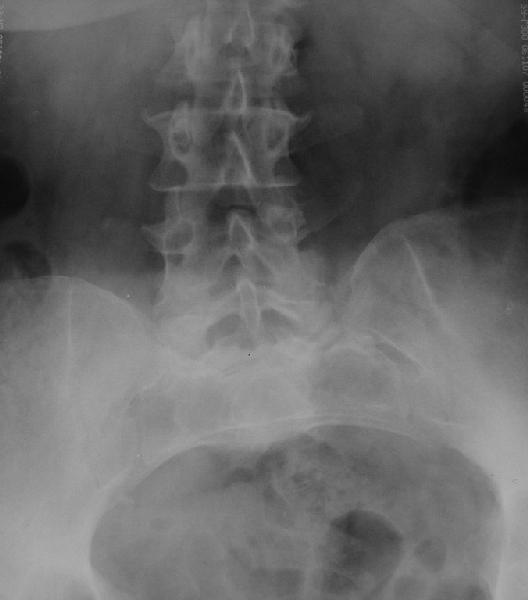

Крайне желательно выполнить МРТ поясничного отдела, так как на представленных рентгенограммах складывается впечатление о спондилолистезе L5,котрый наиболее вероятно и является причной болевого синдрома. Кроме того у болной имеется высокий риск гнойного поражения позвоночника. Только после МРТ можно планировать коррекцию вторичной деформации позвоночника.

Снимок поясничного отдела плохо просматривается на моем компе. Нет ли там спондилолистеза L5-S1?

Если есть, то операция на бедре не поможет. Если нет то есть вопрос - в каком положении контрактура?

Учитывая отсутствие жалоб со стороны тазобедренного сустава - оперативое лечение вряд ли принесет позитивный результат. На первый план выступает спондилолизный спондилолистез (вниматльно посмотрите снимки поясничного отдела)L5 позвонка. На наш взляд больному рекомндовано выполнить транспедикулярную коррекцию и фиксацию сегментов L4-S1 с установкой кейджа в L5-S1.